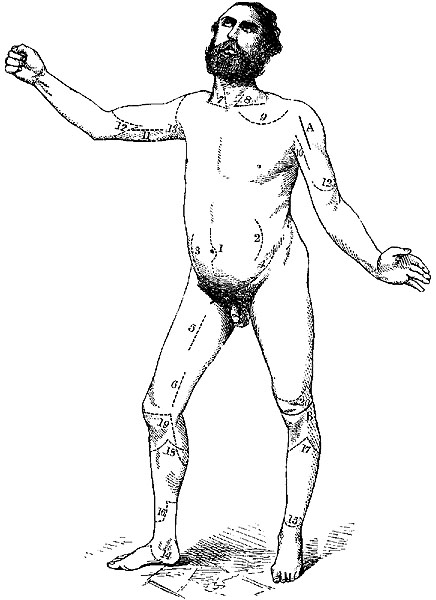

The four plates which precede the letterpress were drawn on wood (from original photographs) by Mr. D.W. Williamson, Melbourne Place, and the lines of incision for the various operations were added by the author.

The rough woodcuts scattered through the work were drawn on wood by the author, and for their roughness he, not his engraver, is responsible. He also hopes that the references in the letterpress will be accepted as sufficient acknowledgment of the true ownership, in those few instances in which the idea of the diagram has been borrowed.

| 1. | Ligature of Aorta—Sir A. Cooper's incision. |

| 2. | Ligature of Aorta—South and Murray's incision. |

| 3. | Ligature of Common Iliac. |

| 4. | Ligature of External Iliac—Sir A. Cooper's. |

| 5. | Ligature of Femoral in Scarpa's triangle. |

| 6. | Ligature of Femoral below Sartorius.[1] |

| 7. | Ligature of Innominate. |

| 8. | Ligature of third part of Left Subclavian. |

| 9. | Ligature of Axillary in its first part. |

| 10. | Ligature of Axillary in its third part. |

| 11. | Ligature of Brachial. |

| 12. | Amputation of Arm by double flaps. |

| 13. | Amputation at Shoulder-joint (1st method), showing portion of skin left uncut till the conclusion of the disarticulation. |

| 14. | Amputation at Ankle-joint by internal flap—Mackenzie's. |

| 15-16. | Amputation of Leg just above the Ankle-joint. |

| 17-18. | Amputation below Knee—modified circular. |

| 19. | Amputation through Condyles of Femur—Syme, and Pl. III. 5. |

| 20. | Amputation at lower third of Thigh—Syme, and Pl. III. 6. |